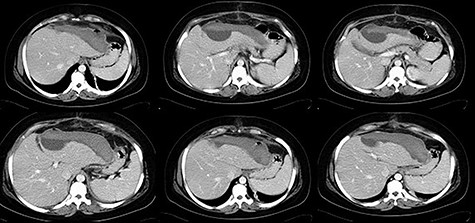

The postoperative period was favorable with lesion regression in serial Computed tomography scan control and was discharged on the 13th postoperative day (Fig. 2).

Thirty-one-year-old pregnant woman, primigravida, with history of obesity, admitted at 35 weeks of gestation due to pain in the right abdomen with 2 weeks of evolution. On admission: hemodynamically stable with tenderness on the right quadrants of the abdomen. The initial blood work only revealed thrombocytopenia (120 × 103/μl) and impaired hepatic function (AST 65 U/L, ALT 88 U/L). The patient was kept on observation, with aggravation of symptoms. Blood work showed anemia (6.9 g/dl), thrombocytopenia (113 × 103/μl) and impaired hepatic function (AST 363 U/L, ALT 399 U/L, LDH 505 U/L). The patient underwent an emergency c-section, during which an extensive hemoperitoneum was observed. It was then converted to median laparotomy in which was observed hepatic rupture of segments V, VI and VII; packing was performed and the abdomen closed. A second-look laparotomy was performed 48 hours later. Two new subcapsular hematomas were found in the left lobe, but without active hemorrhage, which led to the removal of the packing (Figs 3–5).

The patient recovered without complications and was discharged on the 13th postoperative day (Fig. 6).